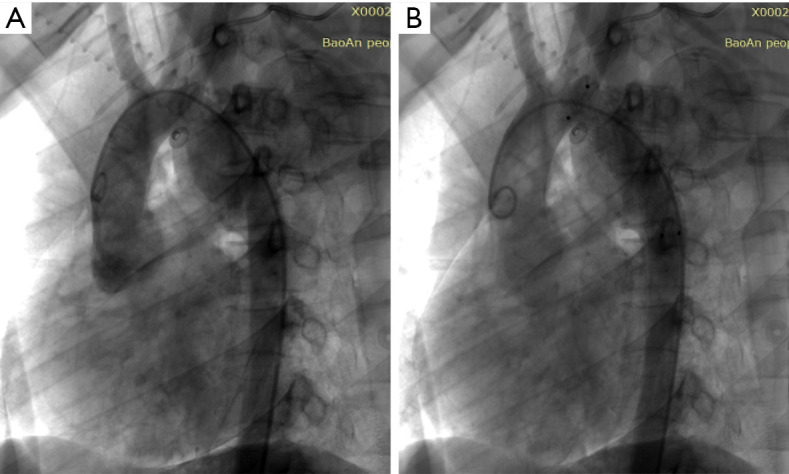

Case description: A 16-year-old male sustained severe multisystem organ injuries after a fall from a five-story building. The patient was critically ill and required intubation during transport. Emergency computed tomography (CT) revealed extensive injuries, including: a descending aorta injury with pseudoaneurysm, bilateral pulmonary contusions with moderate left hemothorax, right pneumothorax, retroperitoneal effusion, right renal contusion with perirenal hematoma, Fractures of the skull base, upper and lower jaw, lumbar spine, sacrum fractures, and severe open wounds in the mouth, right knee joint, and bilateral heels. A multidisciplinary team determined that aortic injury repair should be prioritized. We ultimately performed an unconventional endovascular aortic repair in this adolescent patient. The procedure was completed efficiently without complications, and subsequent interventions successfully addressed the remaining injuries. The patient required a total hospital stay of 733 days and underwent 13 surgical procedures before being successfully discharged following rehabilitation. As of September 2024, the patient remains alive with no complications related to the arterial injury.